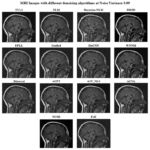

Figure 9 shows a comparative evaluation of various denoising techniques on MRI images at a low Noise Variance (N.V.) of 0.01. BM3D is one of the best options for the medical picture denoising technique, performing very well, preserving delicate anatomical features with low noise artifacts and good contrast. DnCNN comes next and accurately finds a proper balance between removing noise and retention of features and provides sharp edges with soft features. WNNM denoises well, but it has a small quantity of smoothing involved, which results in a fine loss of detailed structural features. Bayesian NLM and NLM both provide fairly modest denoising, while Bayesian NLM retains more of the noise, creating a gritty impression of the image. EPLL and guided filtering are effective methods for noise reduction, but may slightly over-smoothed the data, hiding the small features. Bilateral filtering is not a good noise reducer compared to BM3D or DnCNN, although it provides edge-aware noise reduction. ACPT, AST_NLS, and ACVA show reasonable performance, while ACVA still maintains a good trade-off between anatomical clarity and noise reduction. TVL1 led to excessive smoothing that lost much structural information. FoE and NCSR can hardly eliminate the noise. FoE becomes somewhat grainy because of leftover noise. In all the compared algorithms, it can be concluded that ACPT highly reduced image quality most likely because of excessive processing. However, the highest-quality denoising performance came from BM3D and DnCNN which not only had successfully removed noises from MRI images but also have kept essential anatomical features preserved while Bayesian NLM, TVL1, and FoE perform the poorest.

![]() |

Figure 9: Output of Dataset2 with different denoising algorithms at noise variance 0.01 |